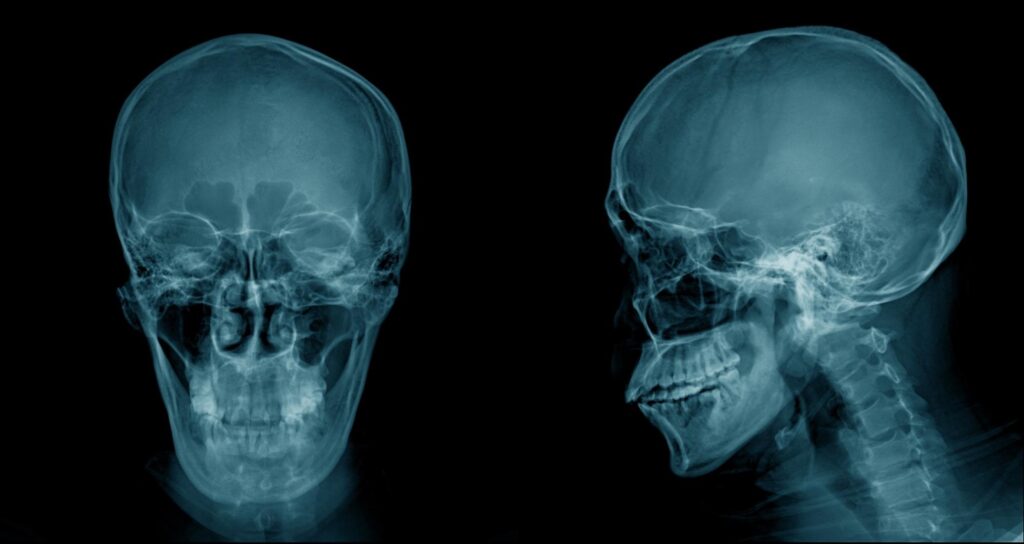

上顎洞とは、頬骨の奥、鼻の横にある空洞のことを指します。左右に一つずつあり、鼻腔と自然孔でつながり、呼吸の際の空気の通り道として機能します。内側はシュナイダー膜という粘膜で覆われています。上顎洞は、前頭洞、篩骨洞、蝶形骨洞とならぶ副鼻腔の一部で、頭部の軽量化や呼吸時の共鳴、吸気の加温と加湿、分泌物の排出にも関与している重要な構造です。

上顎の奥歯の歯根は、この上顎洞のすぐ近くまで伸びていることが多いため、歯科治療と密接に関わっています。特に奥歯を抜いた後に骨が吸収されると、上顎洞がさらに下がり、骨の厚みが極端に薄くなることがあります。